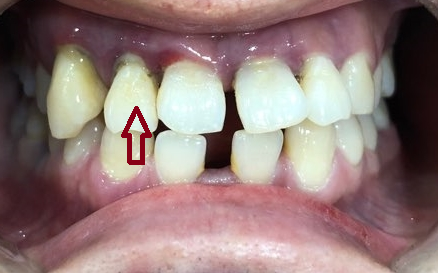

아래 앞니는 일반적인 분들보다 2개가 없는 상태였구요,

위 앞니 중에 화살표 된 치아는 굉장히 많이 흔들리는 상태였습니다.

아무래도 아랫니는 윗니에 어느정도 덮여서 잘 보이지는 않으니

아랫니는 두고 위 치아중 많이 흔들리는 화살표 표시된 치아를 발치하고 이빨 모양자체도 이쁘지 않고 해서 위쪽 앞니는 전체적으로 브릿지를 하기로 하였습니다.